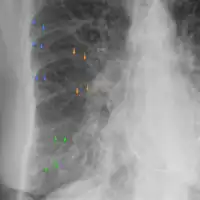

Acute pulmonary edema

Acute pulmonary edema lateral

Low oxygen saturation and disturbed arterial blood gas readings support the proposed diagnosis by suggesting a pulmonary shunt. A chest X-ray will show fluid in the alveolar walls, Kerley B lines, increased vascular shadowing in a classical batwing peri-hilum pattern, upper lobe diversion (increased blood flow to the superior parts of the lung), and possibly pleural effusions. In contrast, patchy alveolar infiltrates are more typically associated with noncardiogenic edema[8]